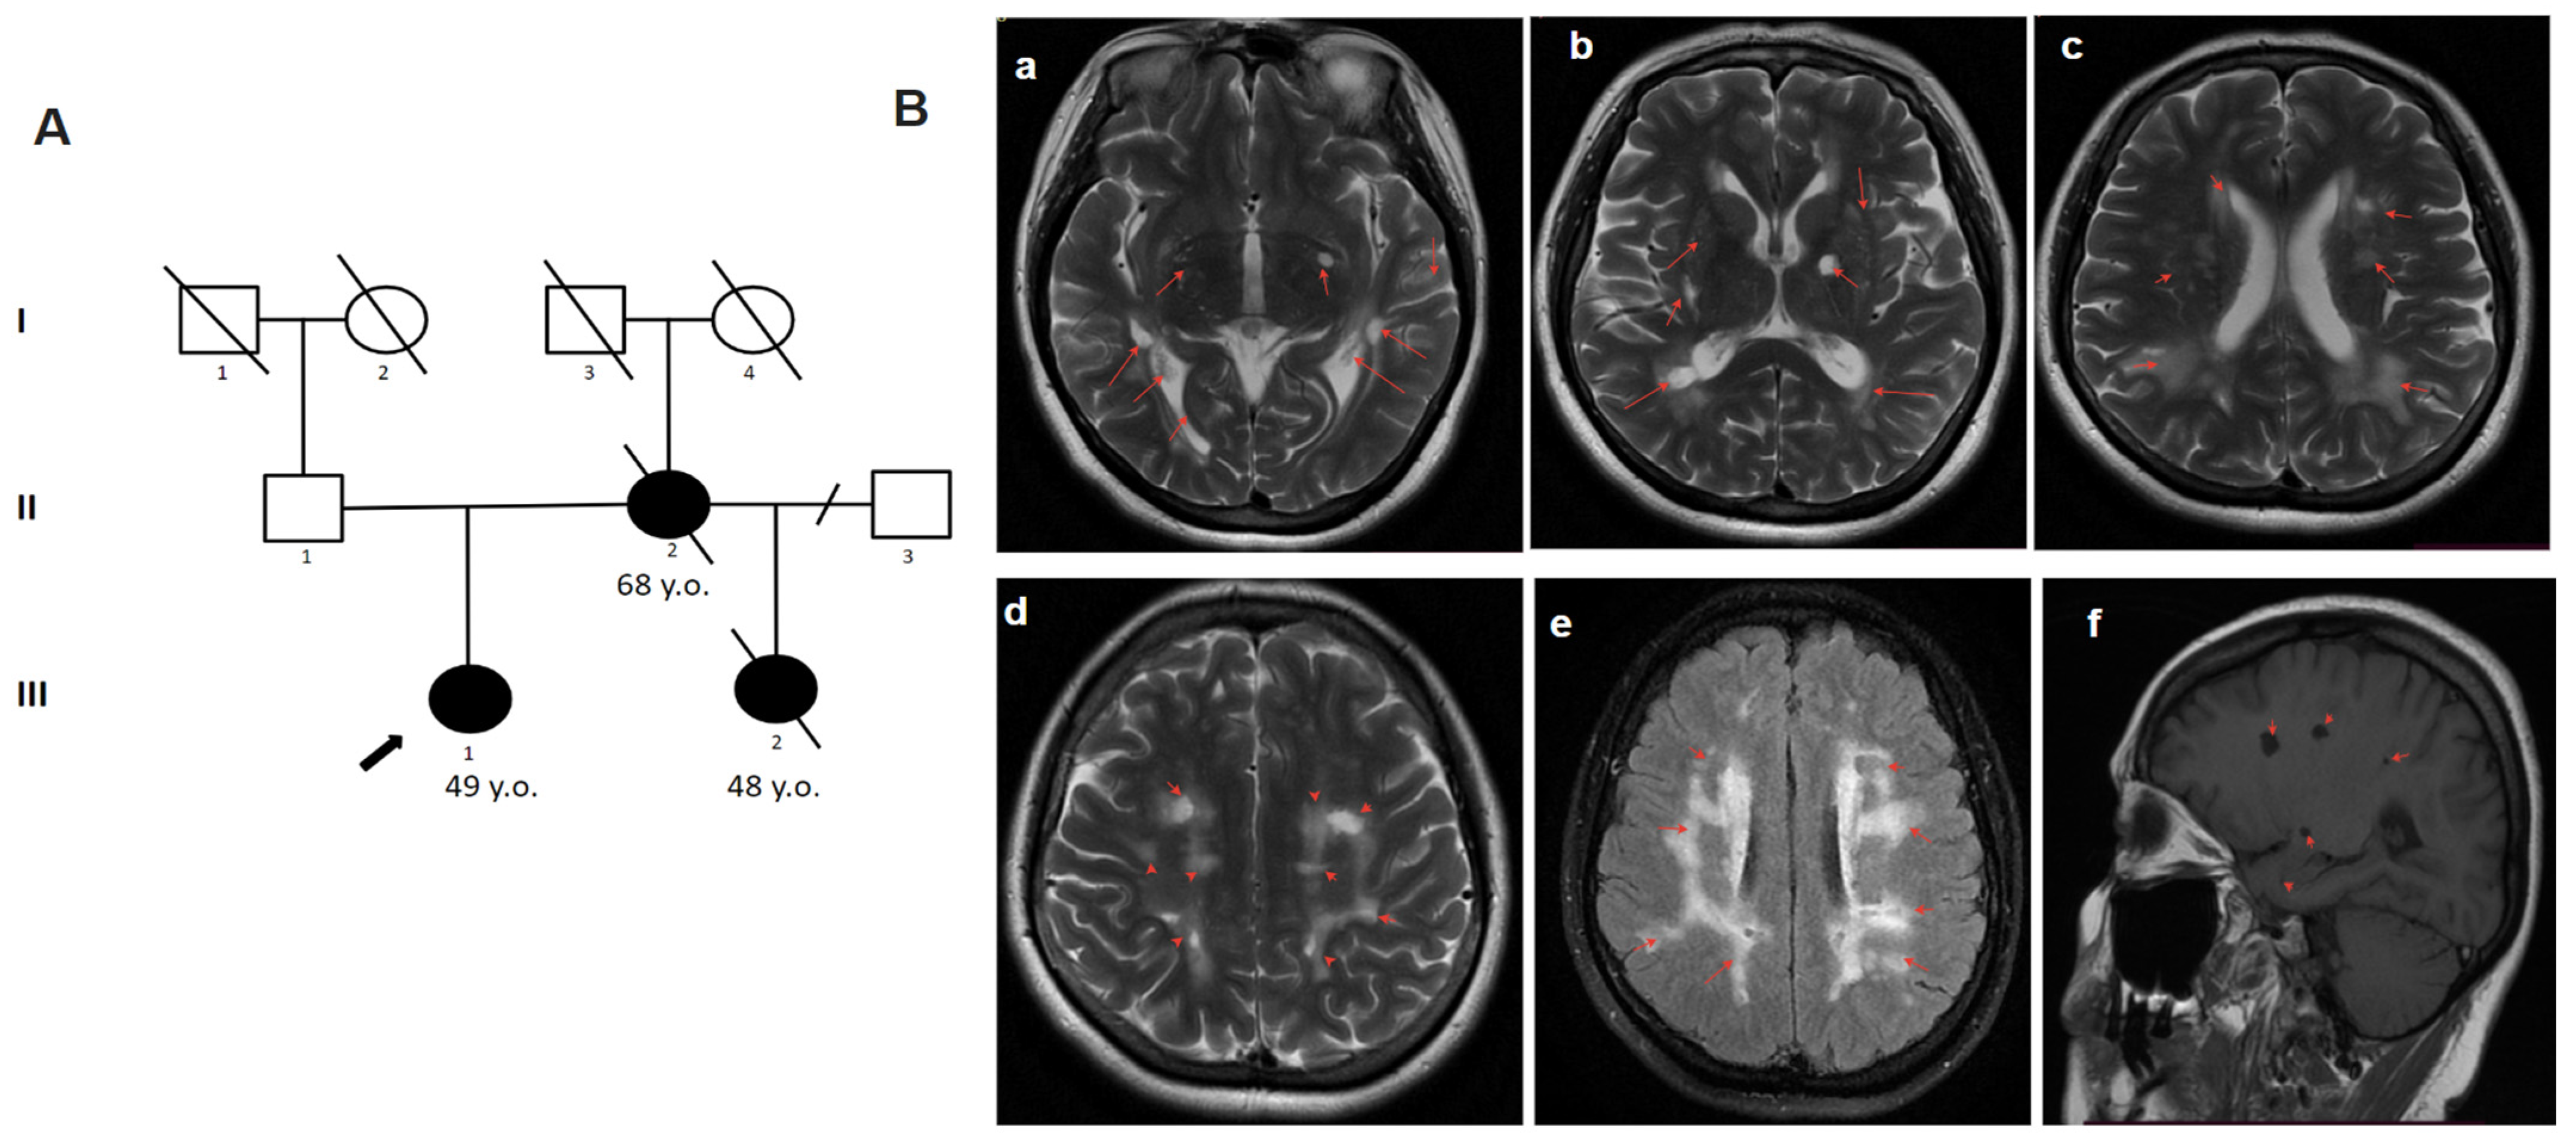

The 49-year-old woman complained of memory impairment, dizziness, concentration difficulties, and ataxia. She considered herself ill from the age of 45 after craniocerebral trauma (she fell down due to dizziness) after which she suffered from headaches. Later, an MRI of the brain (at the age of 48) showed signs of leukopathy. At the age of 49, the disease progressed with a sharp deterioration in the form of dizziness, nausea and vomiting, and with a suspected stroke. On examination, atactic gait and cognitive disturbances were noted. On the brain MRI, multiple white matter hyperintensities and subcortical lacunar lesions (Figure 3) were observed. Blood glucose concentration was elevated: 8.4 mmol/L (6–8.5 mmol/L in dynamics). From the family history, it is known that her sister (half-sibling by mother) died at the age of 48 from a stroke. She had the first stroke at the age of 37 and repeated multiple strokes afterwards. Her mother died at the age of 69 because of a stroke. The patient was referred by a neurologist for consultation at the Research Center for Medical Genetics. The presence of a history of stroke in the mother of the proband and the early age of stroke onset in the sister followed by rapid progression made it possible to suspect CADASIL. The nucleotide variant c.1136G>A, (p.Cys379Tyr) was detected in exon 7 of the NOTCH3 gene in a heterozygous state by targeted panel sequencing (Table 1). Due to the absence of living family members with signs of the disease, it was not possible to assess the phenotype–genotype correlation.

Figure 3.

Pedigree and Neuroimaging features of patient 3. (A)—Pedigree of patient 3.; (B)—MRI images of the brain (III-1); (a–f)—multiple white matter hyperintensities and subcortical lacunar lesions (red arrows).

In the diagnosis of CADASIL, instrumental findings outperform clinical findings. Typical manifestations on MRI include WMH and lacunar infarcts. WMH is a common and early MRI feature of CADASIL. Increased signal intensity in the anterior temporal lobe has high sensitivity and specificity in most cases [15]. This change was detected in two of our patients (patients 1, 2). Signs of recurrent cerebral microbleeds (cortical–subcortical regions, white matter, thalamus, pons) are identified in most patients with CADASIL and are usually localized outside ischemic foci, which allows for considering it almost a pathognomonic sign of the disease [16]. These signs were also present in our patients (patients 1, 2, 3, 4.1). Symmetric periventricular WMH, commonly affecting the anterior temporal lobe, can be observed long before the first symptoms appear [17,18]. By the age of 35, essentially all patients with CADASIL have abnormal MRI findings, which occasionally may occur in the absence of clear clinical features [19,20]. A detailed study of the family history plays an important role in the diagnosis of CADASIL. As stated in patient 1, the key to the diagnosis was a family history. Some patients with a molecularly confirmed diagnosis may remain asymptomatic for a long time, even with well-defined lesions on brain MRI. Brain MRI may be normal early in the disease course, but by the fifth decade, significant white matter changes are the rule rather than the exception [21]. In a study of a cohort of 301 CADASIL patients, it was found that higher WMH associated with the temporal lobes and frontal gyri correlated with a milder course of the disease as compared with WMH in the pyramidal tracts [22]. However, the question of correlation between the degree of WMH changes and the severity of CADASIL patients remains open today and requires further study.